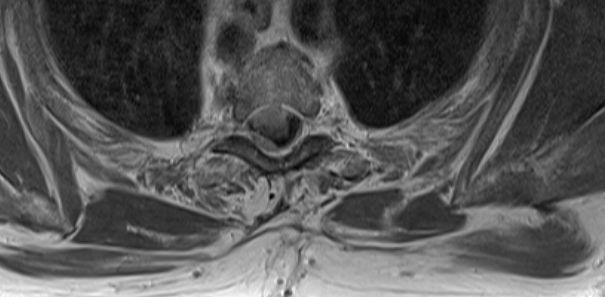

| Rückenmark |

76-jährige Frau mit Rezidiv eines Rückenmarks-Meningeoms. Erstmanifestation vor 17 Jahren. Rezidive von 12, 6 und 3 Jahren jeweils operativ beherrscht. Seit einem Jahr erneut Schmerzen zwischen den Schulterblättern und Druckgefühl im Thoraxbereich. Reduzierter AZ und adipöser EZ. KHK, VHF, Hypertonie, Hypothyreose. Auf Rollator angewiesen. Zunehmende Gangunsicherheit und Kribbeln in den Beinen. Klopfschmerz im Bereich von BWK2-5 stark auslösbar. Die Schmerzen strahlen zeitweise in die Schulterblätter aus. | ![]() | |||||

![]() |

![]() | ||||||